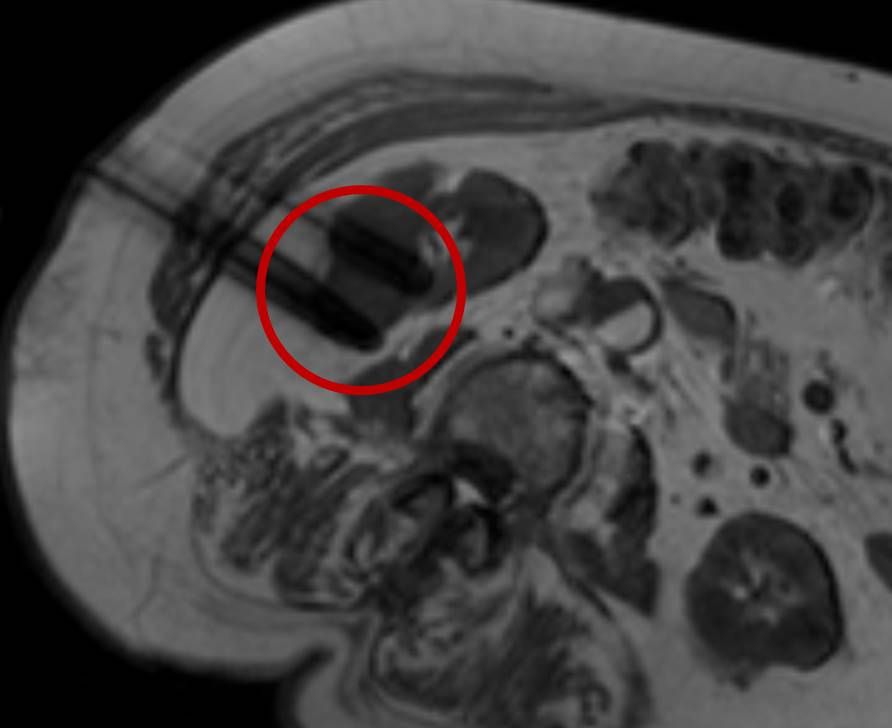

Präoperative Tumormarkierung

Eine Voraussetzung für die vollständige chirurgische Entfernung von Knochen- und Weichteiltumoren ist die präzise Erkennung der Tumorausdehnung und der Tumorgrenzen. Mit der Kernspintomographie (MRT) kann das Tumorgewebe exzellent von gesundem Gewebe abgegrenzt werden und somit die Ausdehnung vor der Operation bestimmt werden. Nach der kernspintomographischen Bestimmung der Tumorausdehnung werden unter kontinuierlicher MRT-Bildgebung die Grenzen des Tumors markiert. Die Marker werden mit einer Nadel ins angrenzende gesunde Gewebe eingebracht. Die Markierung kann am Tage vor der Operation durchgeführt werden. Alternativ ist die Tumormarkierung auch mit anderen bildgebenden Verfahren möglich, z.B. mit der Computertomographie oder dem Ultraschall.

Abbildung: Bei diesem Patienten wurde ein im Röntgen nur schlecht sichtbarer Knochentumor vor der Operation unter MRT-Kontrolle mit kleinen röntgendichten Spiralen („Coils“) markiert. Damit hat der Operateur eine optimale Darstellung des Tumorbereichs bzw. der Tumorgrenzen und kann gezielter, schonender und effektiver operieren.